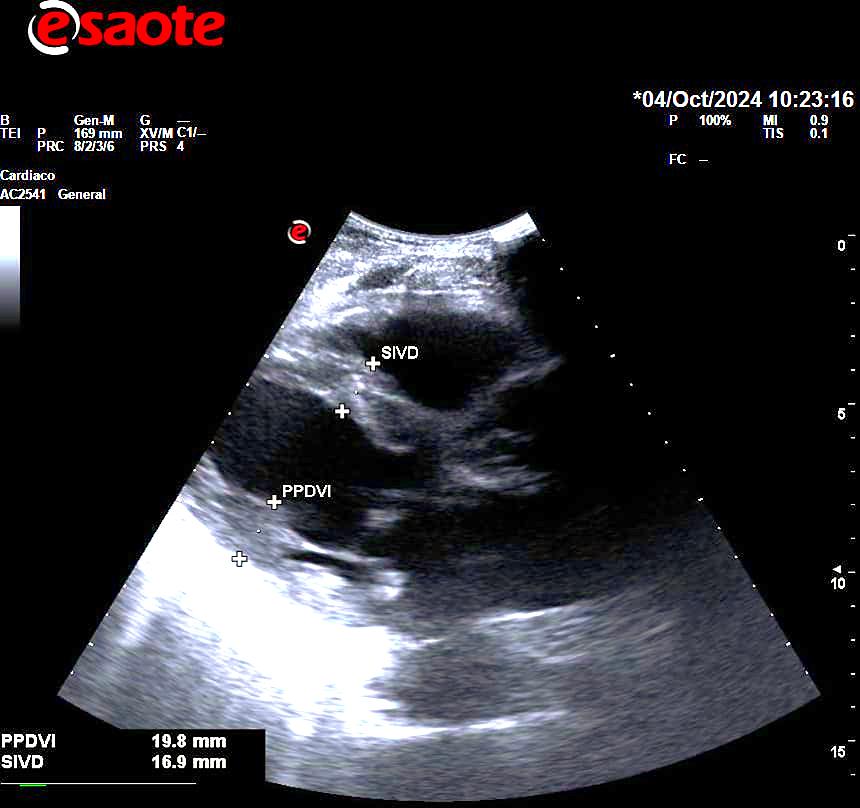

En la ecocardioscopia, se aprecia leve dilatación de aurícula izquierda, septo interventricular de 18 mm sin obstrucción del tracto de salida, FEVI estimada mayor del 55% sin segmentarismos ni discinesias, raíz aórtica normal, válvula aórtica trivalva, buena apertura de válvula mitral, no derrame pericárdico.